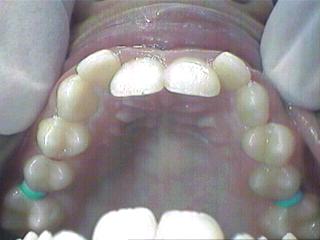

Malocclusion [Div.I]

Before Treatment Intra Oral